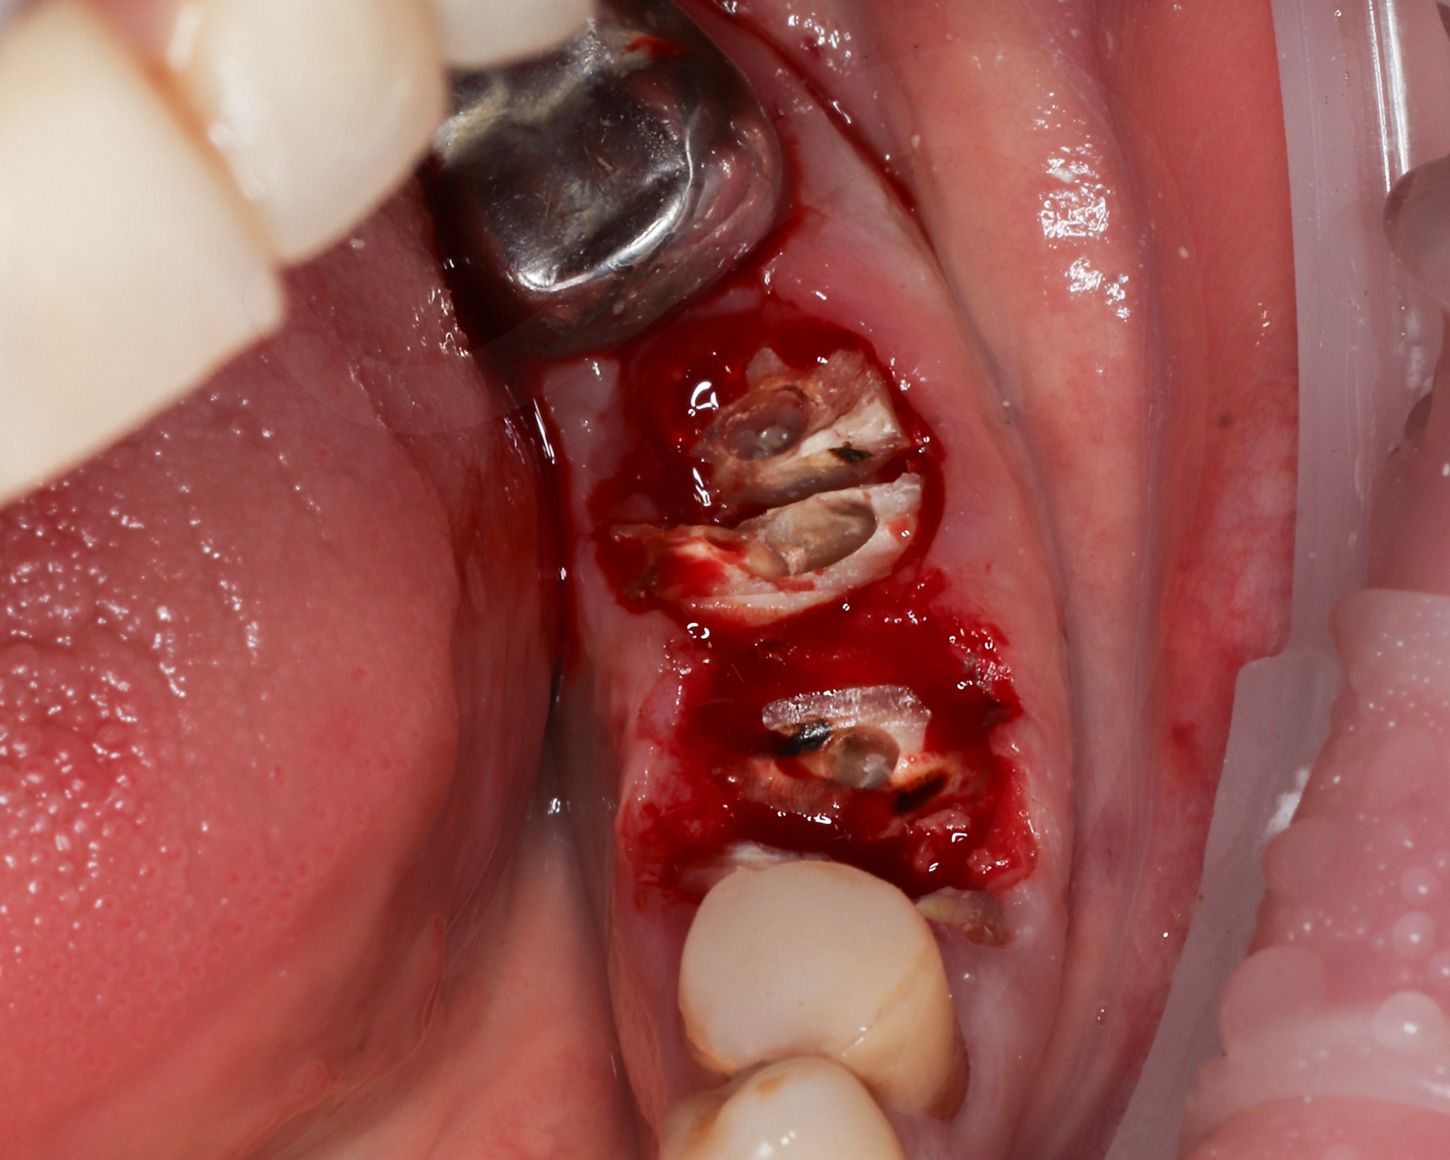

Поскольку сохранение альвеолярной кости имеет решающее значение для успеха немедленной имплантации, перед извлечением корней между ними подготовили фрезами ложа под имплантаты, чтобы избежать деформации кости на пути бурения, а затем с особой осторожностью удалили корни (Илл. 2).

Стенки лунки сохранили нетронутыми и тщательно освободили от грануляционной ткани, промыли стерильным раствором.

Иллюстрация 2